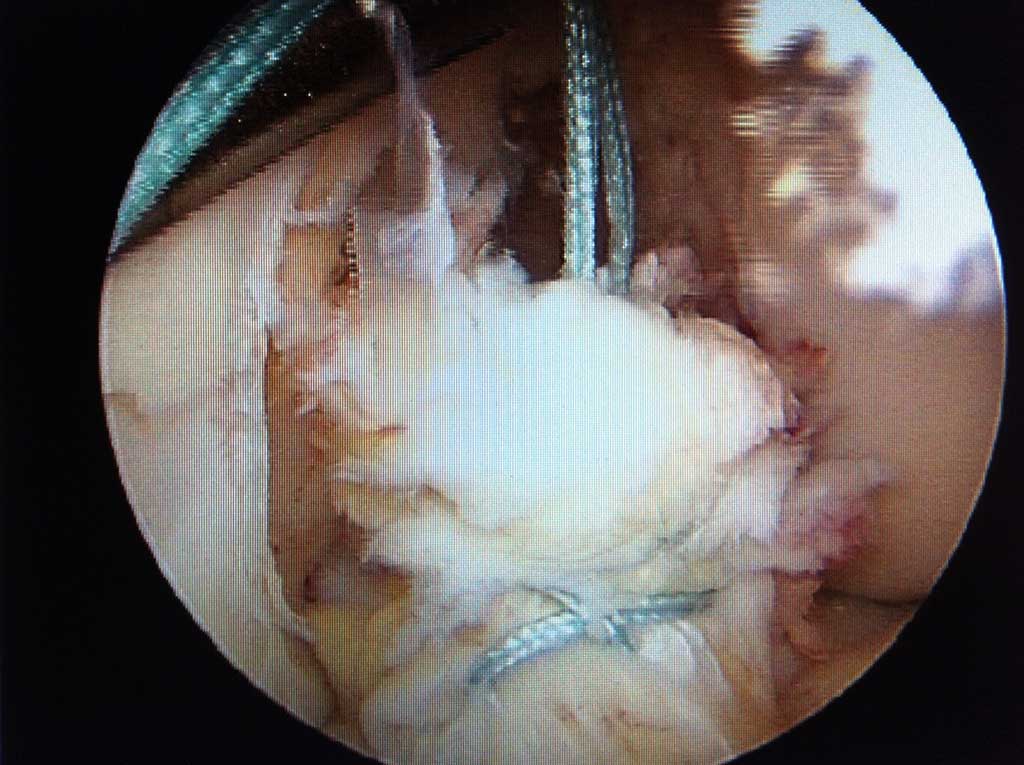

Arthroskopische Meniskus - Teilentfernung

Wie läuft die Operation ab ?

Es handelt sich dabei um einen ambulanten Eingriff in unserer OCD Klinik. Die Operation wird in Spinatanästhesie durchgeführt und dauert einige Minuten. Während des Eingriffes kann dem Patienten, auf Wunsch, auch das operative Vorgehen auf grossem LCD Monitor erklärt werden.

Nach zirka 2 Stunden kann der Patient wieder nach Hause abgeholt werden.

Arthroskopische Meniskusnaht

Es ist in unseren Händen ebenfalls ein ambulanter Eingriff in OCD Klinik im Maximilium, welcher je nach Ausdehnung des Risses zwischen 15-30 Minuten in Spinatanästhesie dauert. Der Riss wird in s.g. " all inside " Technik genäht, so dass nicht mehr als 2-3 winzige Stichinzisionen am Knie für den ganzen Eingriff notwendig sind und keine zusätzlichen seitlichen Zugänge angelegt werden müssen. Nicht selten wird auch in der gleichen Sitzung, ebenfalls rein arthoroskopisch das gerissene vordere oder hintere Kreuzband genäht oder mit körpereigener/-n Sehne/-n ersetz.